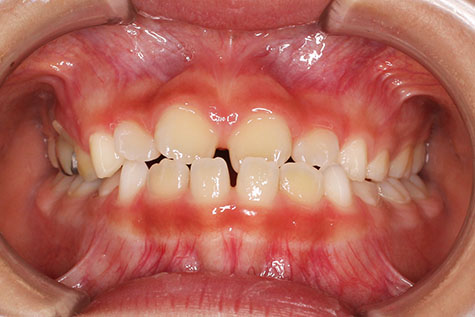

| 小児矯正から始められた受け口傾向の患者さんです。

前歯が反対咬合で、永久歯の萌出スペース不足による上顎前歯部の叢生(がたつき)が予測できる患者さん。 骨格的に、上顎と比べ下顎が大きく、成長によっては外科手術になる可能性もありましたが、 外科手術はせず、矯正治療のみで咬み合わせを改善しています。 小児矯正で、前歯部の被蓋(重なり)の改善まで治療を行い、下顎の成長を観察した後に、 永久歯列から、マルチブラケット装置により非抜歯にて配列しました。 来院間隔1.5カ月でしたが、平均より短く治療を終えることが出来ました。 マルチブラケット 動的治療期間 2年1か月 調整回数14回